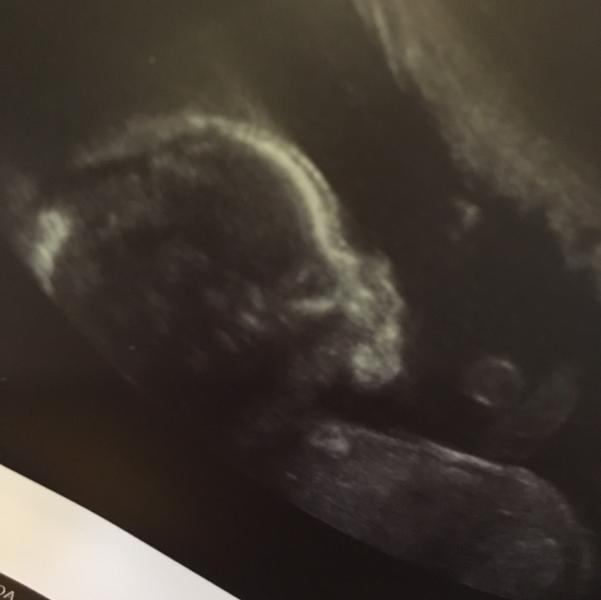

Ну вот мы и узнали как дела у плода нашей любви))) всё в норме! Наш богатырь весит 300гр)) определили пол с полной уверенностью, показали его мужское достоинство😊 узи делали на краснофлотской у Кусакиной, приятная женщина, всё подробно показала и рассказала! Узи по времени было около 15-20 минут. Дочка с мужем сидели разглядывали экран с ляликом с большим интересном)) всё понравилось 👍 муж в восторге, дедушка так обрадовался новости что расплакался 🤗 все счастливы)) уже идут споры по поводу имен...